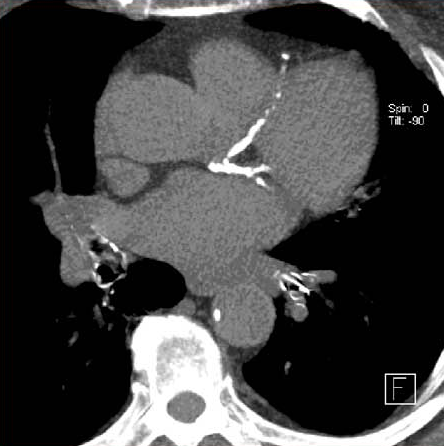

Tasas de procedimientos posteriores y complicaciones asociadas con el rastreo de cáncer de pulmón en la práctica clínica

08 enero 2024

En la práctica habitual, las tasas de procedimientos posteriores y de complicaciones del rastreo del cáncer de pulmón con tomografía computada son sustancialmente más altas que las observadas en el ensayo clínico NLST. Es probable que sea necesario evaluar y mejorar la gestión del diagnóstico para garantizar que los beneficios de las pruebas de detección superen los posibles daños. Annals of Internal Medicine, 2 de enero de 2024.